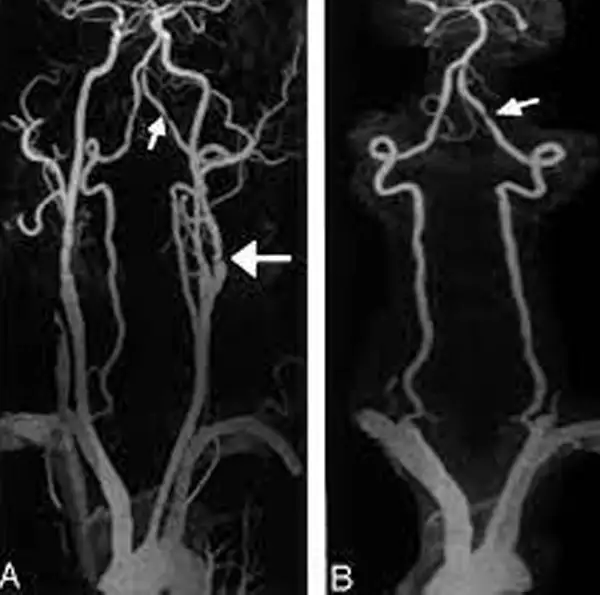

MR Angiography Carotid is the test of the neck in which a magnetic field, radio waves and a computer are used to take images of carotid arteries. It takes two three-dimensional images of the blood vessels.

MR Angiography Carotid is conducted to evaluate the presence of any blockage or narrowing in the carotid arteries. Determine the risk of future stroke and the need for further treatment to lower your stroke risk.